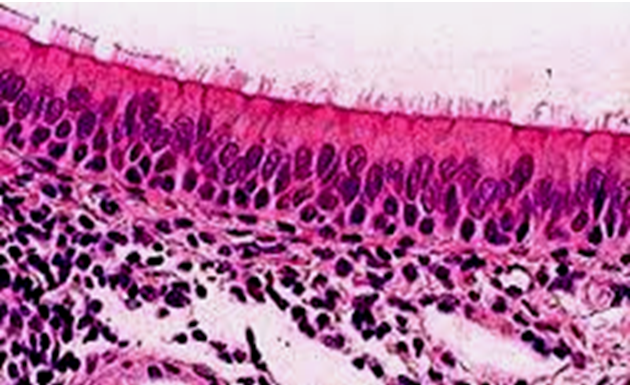

LM picture of pseudostratified columnar ciliated epithelium